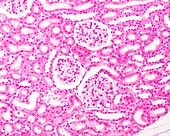

12360983 - Kidney, light micrograph

12360952 - Convoluted tubules, light micrograph

12360908 - Kidney glomeruli, light micrograph